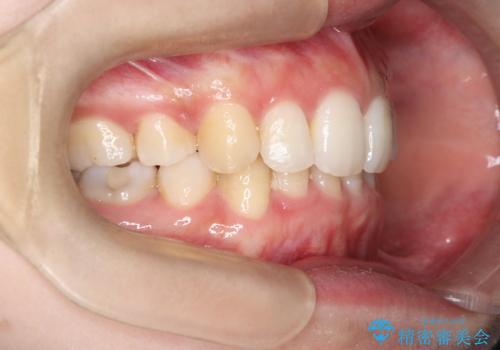

今回の治療では、重度の叢生を改善するため、まず計画通り上下左右4本の小臼歯を抜歯し、歯を並べるための十分なスペースを確保しました。装置には透明で取り外し可能なインビザラインを使用。抜歯によってできたスペースを最大限に活用し、マウスピースを定期的に交換しながら、デコボコを解消しつつ、前歯を効果的に後退させました。

治療の結果、長年の悩みであった重度の歯のがたつきが解消され、口元の突出感も改善。機能的にも安定し、審美的にも美しい、理想的な歯並びを獲得していただけました。